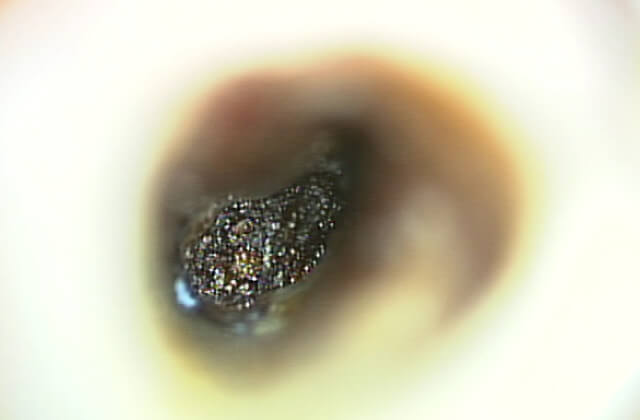

歯の周りのアゴの骨が溶けてなくなり膿が溜まっています(黒く写っている所)

このような事を防ぐためには、信頼できる技術を持つ専門医がマイクロエンドを行う医療機関を受診し、根管に存在する細菌を確実に取り除く根管治療が必要になります。